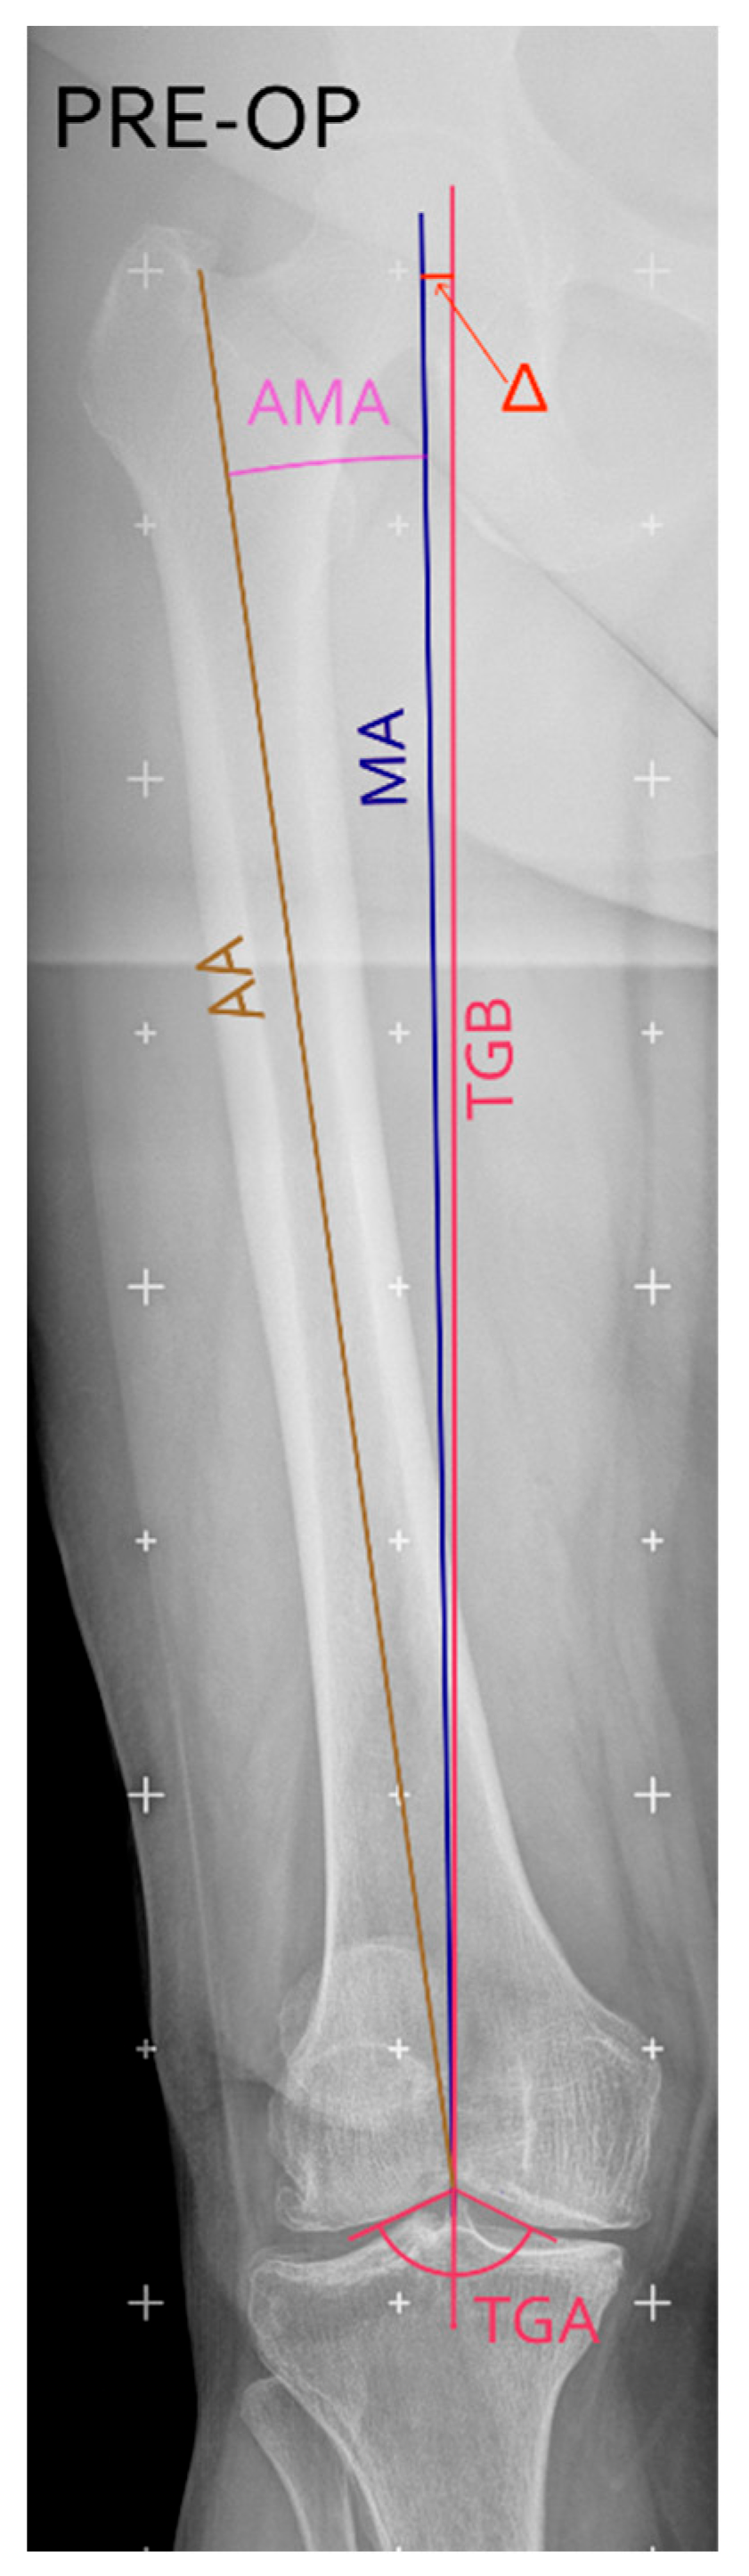

After the identification of bone landmarks, hip-knee angle (HKA), anatomical axis (AA), mechanical axis (MA), anatomical mechanical angle (AMA), and mechanical lateral distal femoral angles (mLDFA) were measured using standardized techniques to guide bone resections and implant positioning [20]. Also, the TGB was measured on long-leg coronal X-rays, as previously described [20]. In brief, the trochlear groove angle (TGA) was determined by drawing two tangential lines along the medial and lateral aspects of the trochlear groove from the radiographic apical midpoint of the intercondylar groove (see Figure 1a). The TGB was then drawn as the bisector of the TGA (purple vertical line in Figure 1a).

The distal femoral cut (purple horizontal line in Figure 1b) was planned perpendicular to the TGB. Once the distal femoral cut was identified, the MA was drawn and the planned mLDFA (mLDFAp) was defined as the angle between the planned cut and the MA [21].

Lastly, the angle between MA and TGB, which was expressed as Delta (∆), was computed (see Figure 1b). When TGB was medial to MA, ∆ took positive values; conversely, when TGB was lateral to MA, ∆ took negative values.

In the event an intramedullary guide was used, the resection had to be opportunely adjusted considering the preoperatively calculated AMA angle (see Figure 2), according to the following rule:

intramedullary guide angle = AMA + ∆

Figure 1. Zoomed versions of the right knee in a pre-operative long-leg coronal X-ray, with the representation of the mechanical axis (MA, blue line); the trochlear groove bisector (TGB, purple line); trochlear groove angle (TGA) (a) and planned mechanical distal femoral (mLDFAp, green angle) (b). Figure created with Inkscape (version 1.4.3, The Inkscape Project, Boston, MA, USA).